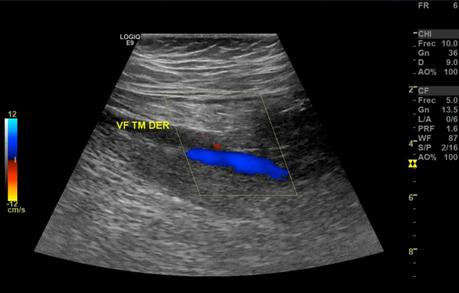

Se realizaron múltiples barridos ecográficos con transductor lineal de 9 MHz en escala de grises, Doppler color y espectral, con paciente en decúbito supino, efectuando valoración del sistema venoso superficial y profundo, observando siguientes hallazgos:

En el sistema venoso profundo, la valoración de las venas femoral común, femoral, femoral profunda, poplíteas, todas ellas presentaron flujo espontáneo y respiratorio fasico unidireccional con adecuada competencia valvular.